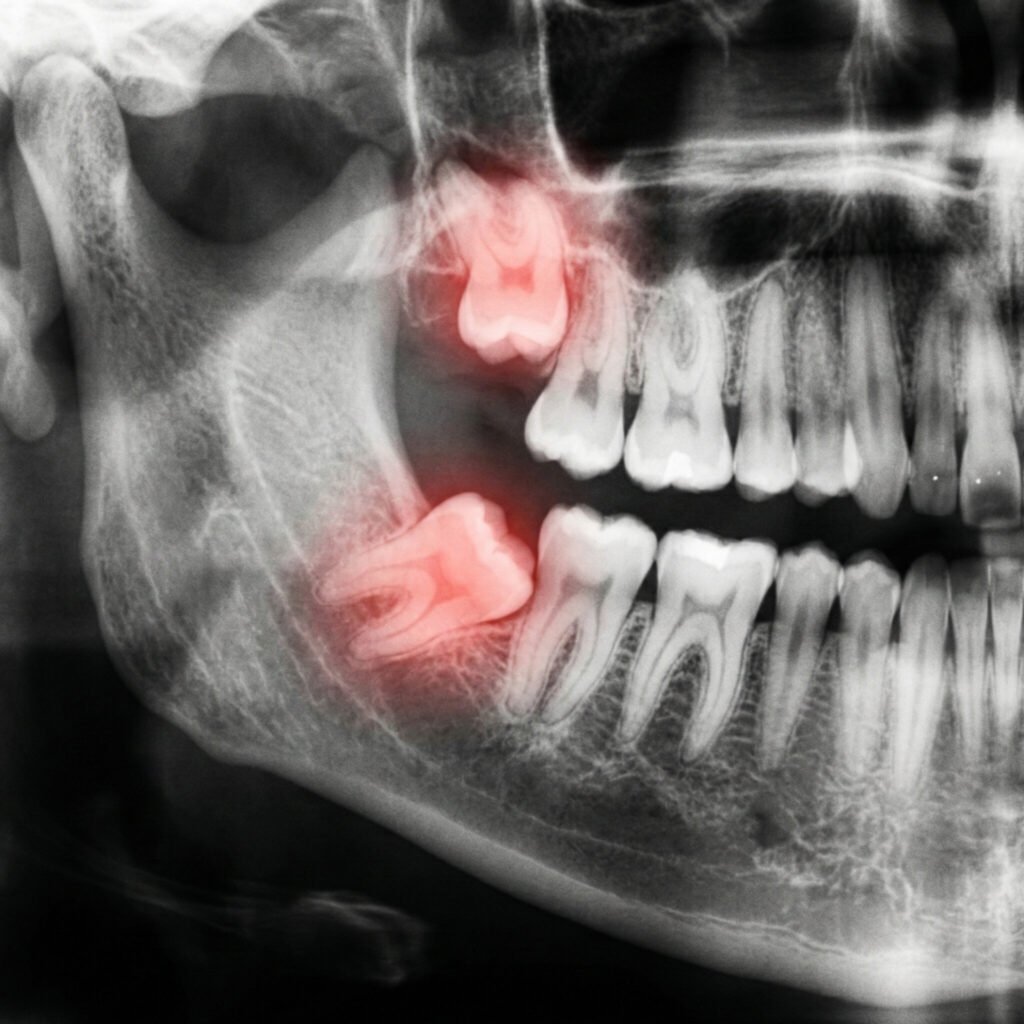

radiographie dentaire

Radiographies Dentaires

Nous disposons d’une technologie avancée de radiographie dentaire pour une expertise précise.

dents de sagesse

Traitez les problèmes de dents de sagesse grâce à nos extractions et soins spécialisés.